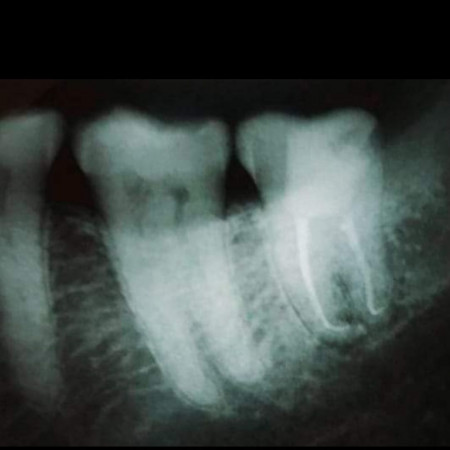

Advanced Complex Root Canal Treatments And Re-treatments

Not all root canal treatments are straightforward. The shape and degree of formation of the root of some teeth require expert intervention. We are proud to house some of the best-trained specialists at Danthaja to handle such cases. Furthermore, failed root canal treated cases done elsewhere, which need re-treatment will also be handled by our specialists.

- MTA treatment cases

- Difficult anatomy cases

- Re-treatment cases